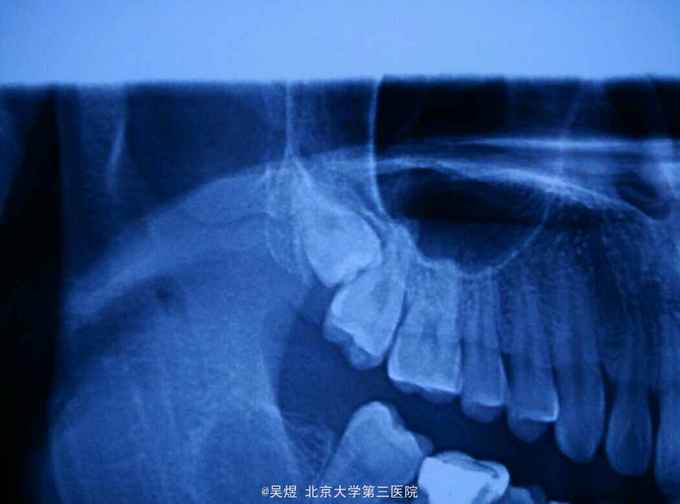

18埋伏,表面牙龈未见异常。曲断示:18高位水平阻生,牙冠与17及上颌窦关系密切。